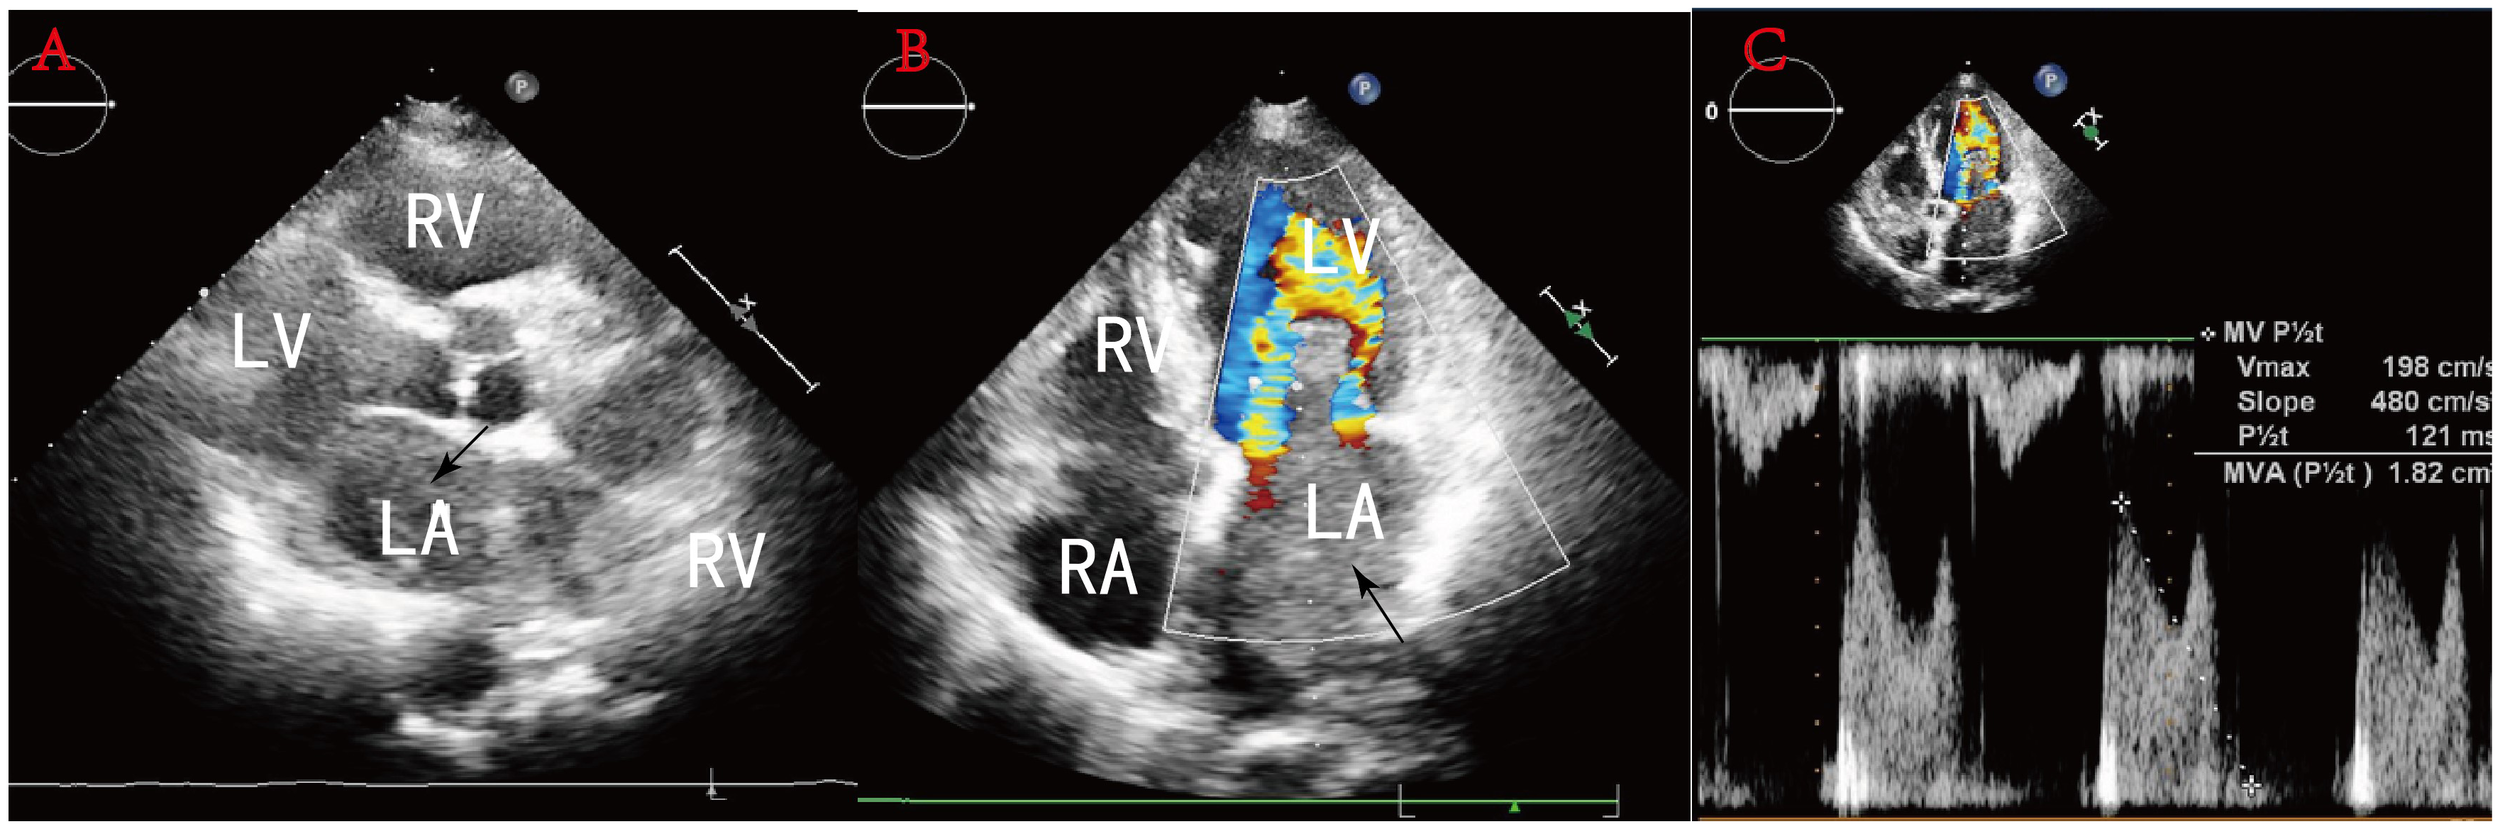

A 78-year-old woman presented to the outpatient clinic for “COVID-19” infection. Transthoracic echocardiography (TTE) revealed a left atrial hypoechoic mass measuring 85 mm × 55 mm × 35 mm. This mass was located in the left atrium and had a wide base connecting it to the left atrial wall. During diastole, part of the hypoechoic mass was visible, allowing blood flow to be expelled into the left ventricle through the mitral valve orifice. Additionally, mild mitral regurgitation was observed. Notably, TTE showed that the left ventricular ejection fraction (LVEF) was preserved at 68% (Figure 1), and the patient did not present any symptoms regarding the cardiovascular system. An enhanced computed tomography (CT) scan of the chest, abdomen, and coronary arteries on admission showed a filling defect in the left atrium, which was likewise considered to be atrial tethering (Figure 2). Cardiac CT and coronary angiography showed coronary atherosclerosis, including moderate stenosis of the left anterior descending branch in the middle part of the lumen and slight stenosis of the distal part of the right coronary artery. In addition, several suspicious lymph nodes were found in the mediastinum and adjacent to the great vessels. Laboratory tests revealed an N-terminal pro-B-type natriuretic peptide (NT-pro-BNP) level of 1030 pg/mL (normal range <450 pg/mL for those under 50 years old and <900 pg/mL for those over 50 years old) and a fibrinogen level of 4.88 g/L (normal range 2–4 g/L). The remainder of the admission tests did not indicate any abnormalities.

Figure 1

(A) Sternal fat left ventricular long-axis view: a hypoechoic mass is seen in the left atrium, and some of this hypoechoic mass is seen entering the left ventricle during diastole through the mitral orifice. (B) No obvious blood flow is seen in the mass. (C) Pulsed Doppler flow spectra at the mitral valve orifice: mild mitral regurgitation.